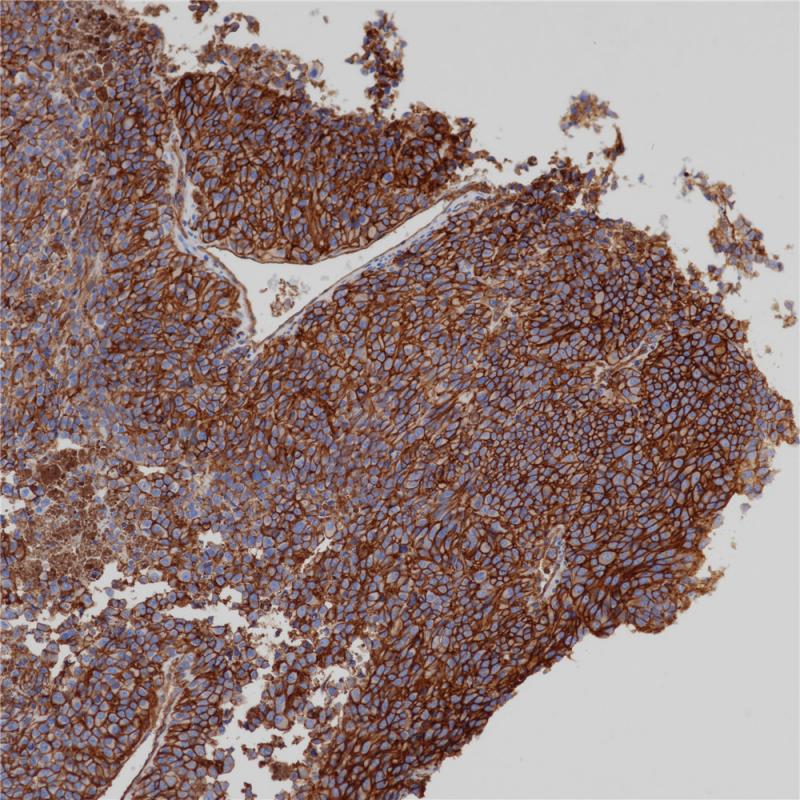

宫颈MHCⅠ(BP6234)染色

主要组织相容性复合体(MHC)是染色体上由紧密连接的高度多态的基因位点组成的遗传区域。MHC分为Ⅰ类、Ⅱ类和Ⅲ类基因区域。MHCⅠ广泛分布于几乎所有有核细胞的表面,包括正常组织中的脾脏、淋巴结、胸腺淋巴细胞、皮肤、肺、肾、肝和心脏和肿瘤组织。MHC Ⅰ分子分型与器官移植与骨髓移植的匹配,以及多种自身免疫性疾病相关。

亚细胞定位

细胞膜